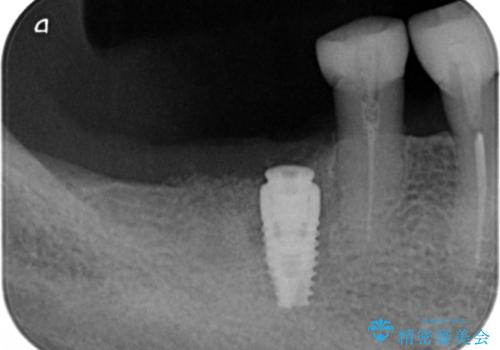

患者様のご希望により、抜歯後インプラント治療を行いました。

- ¥550,000 (インプラント、骨増生、アバットメント、クラウン) ※税込費用は治療当時の料金となります

奥歯でしっかりと咬むことができるようになり、大変喜んで頂けました。

クラウンの種類:オールセラミッククラウン スタンダード